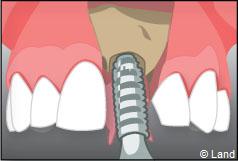

Un implant dentaire est une racine artificielle, placée par le chirurgien-dentiste dans l’os alvéolaire de l’un des maxillaires en remplacement de la racine d’une dent extraite, qui servira de support à une prothèse. Sa forme est généralement cylindrique ou légèrement conique, ressemblant à une vis, en titane ou en zircone, avec une connexion au niveau supérieur, à l’emplacement de la gencive, pour permettre la pose d’un élément prothétique par vissage ou scellement. Son diamètre varie entre 3 et 5 mm et sa longueur entre 8 et 15 mm. La pose d’un implant, réalisée sous anesthésie locale, est totalement indolore. Elle se pratique au cabinet dentaire ou en clinique.

L’implant est placé dans l’os le plus souvent par vissage et doit avoir une liaison forte avec l’os. Le praticien replace alors la gencive et pose des points de suture.

Il faut attendre après la pose de l’implant, l’ostéo-intégration, qui peut durer plusieurs mois. L’implant va se souder complètement avec l’os et contrairement à la dent naturelle, il n’y a pas de souplesse ou de mobilité physiologique dues au ligament alvéolo-dentaire.